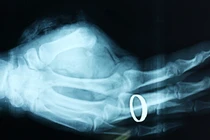

Tại khoa cấp cứu A9, bệnh nhân được thở máy qua ống nội khí quản, dùng thuốc an thần và truyền dịch. Theo kết quả thăm khám của bác sĩ bệnh viện Bạch Mai thì tại những phần cơ thể bị sét đánh hoặc ảnh hưởng do sét đánh như vùng cổ, ngực và bụng trái xuất hiện các tổn thương phỏng rộp đã tróc da. Kết quả chụp CT sọ não có hình ảnh xuất huyết và nghi ngờ bệnh nhân này có tổn thương sợi trục thần kinh. Điều may mắn là tim thai trong bụng thai phụ vẫn còn tốt.